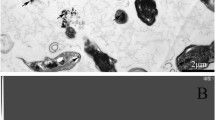

Histology of liver, kidney and lung tissues of Se-treated mice has been shown in Fig. 1. Histopathological examination of Nano-Se treated mice showed normal architecture of liver, kidney and lung tissues similar to that of control animals. Absence of detrimental effects of chronic administration of Nano-Se for a period of 28 days was noted. The cellular structure remained unaltered with the absence of necrosis, inflammation or other lesions. In liver and kidney tissues of mice exposed to inorganic selenium resulted in infiltration of mononuclear cells with pycnosis and renal necrosis. The damages were more in liver and kidney tissues of mice treated with organic selenium exhibiting dilated blood sinusoids in liver and glomerular congestion and renal necrosis in kidney. Lung sections were affected with thickened alveolar septa, congestion and distortion of alveoli with edema in inorganic and organic Se-exposed mice lung tissues.

Histopathological observations of liver, kidney and lung tissue sections of mice gavaged with 2 mg Se/kg b.wt. for 28 consecutive days. Magnification × 200. a Liver section of the vehicle control group; b liver section of inorganic selenium group showing leukocyte infiltration (LI), pyknotic nuclei (PK); c liver section of organic selenium showing cytoplasmic vacuole (CV), dilated blood sinusoids (DBS); d liver section of nano selenium showing normal liver architecture same as vehicle control group; e kidney section of vehicle control group showing proximal (P), distal (D) tubule; f kidney section of inorganic selenium group showing leukocyte infiltration (LI), renal necrosis (RN); g kidney section of organic selenium group showing renal necrosis (RN), glomerular congestion (GC); h kidney section of nano selenium showing normal kidney architecture same as vehicle control group; i lung section of the vehicle control group (arrow) showing normal alveolar architecture without any epithelial damage; j lungs section of inorganic selenium group (thick arrow) showing thickened alveolar septa; k lungs section of organic selenium (arrow) showing congestion and distortion of alveoli with edema formation; l lungs section of Nano selenium showing normal lung architecture same as vehicle control group

Hematology and clinical chemistry of bone marrow and spleen confirm that Nano-Se did not affect Hb level, bone marrow and spleen cell counts. Normal architecture of liver, kidney and lung tissues similar to that of control animals were observed in histopathological examination of Nano-Se treated mice. In liver and kidney tissues of mice exposed to organic selenium for 28 consecutive days, the damages were more pronounced than the inorganic Se-treated mice. Lung sections were affected with thickened alveolar septa, congestion and distortion of alveoli with edema in inorganic and organic Se-exposed mice lung tissues.